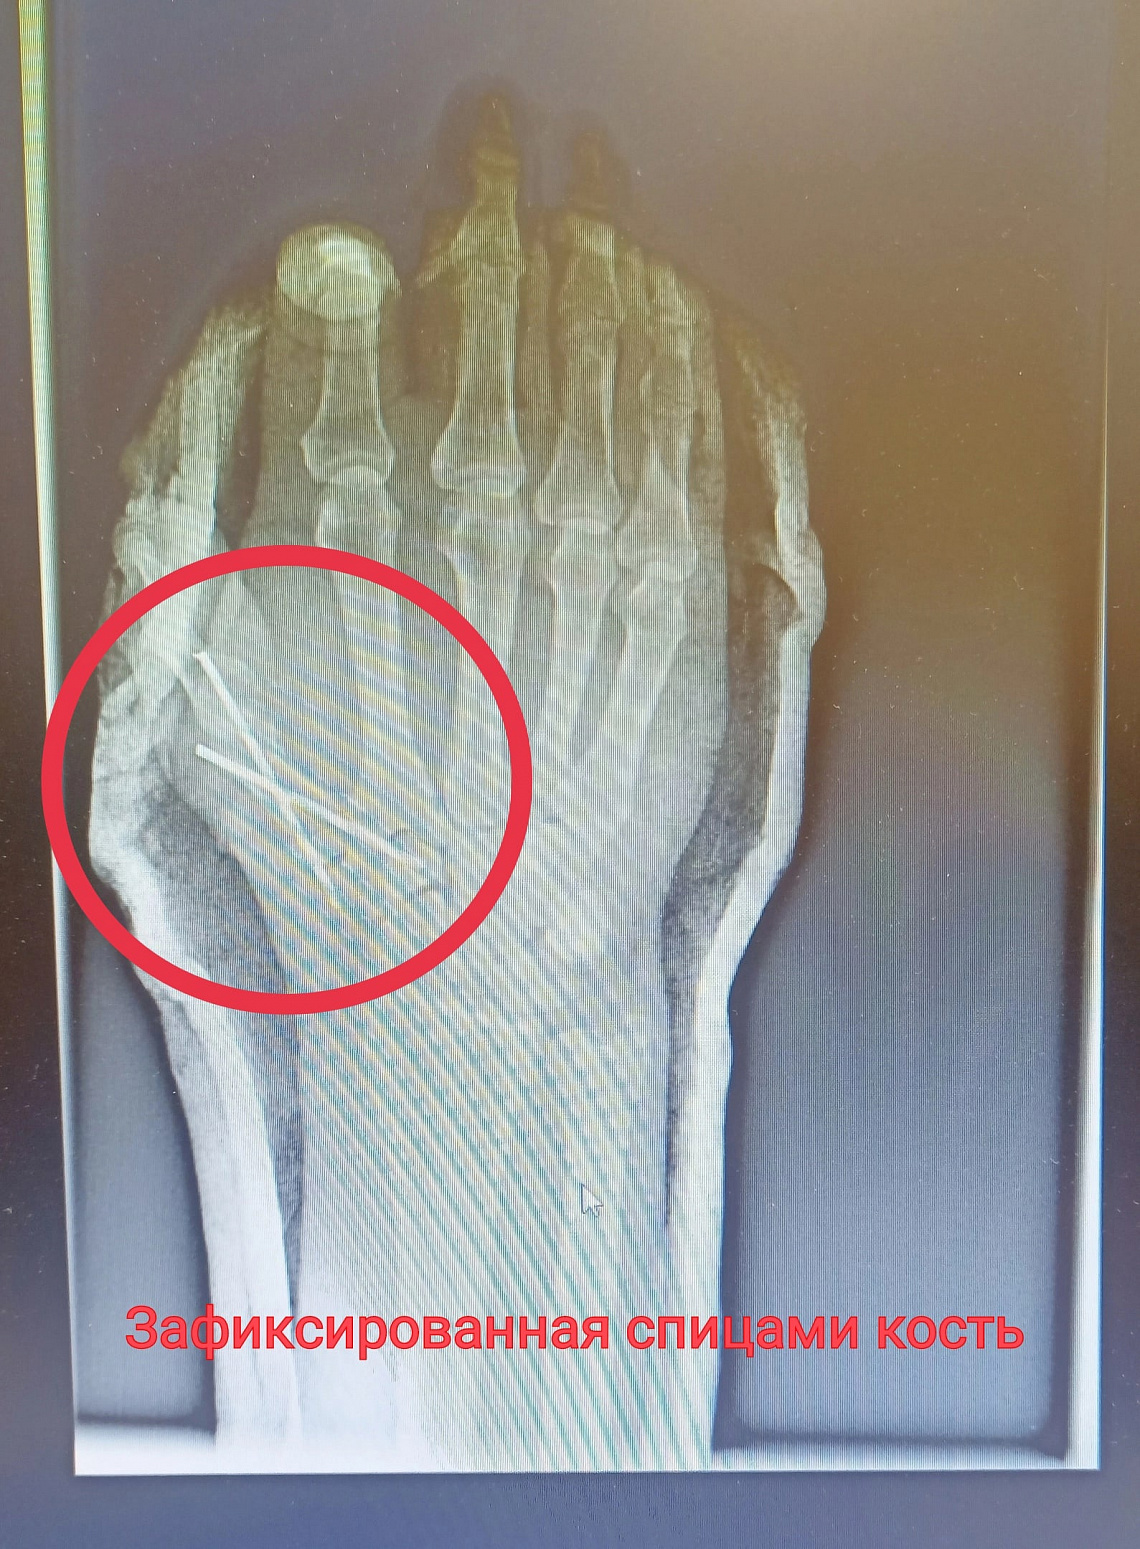

Мужчине повезло, рядом была жена, которая сразу же наложила жгут, перемотала рану и привезла супруга в приёмный покой НЦРМБ. В экстренном порядке мужчину прооперировал врач травматолог-ортопед Марат Шахбанов, ему помогала операционная медицинская сестра Энже Газизова. Травма оказалась сложной, мужчина мог лишиться большого пальца, который почти полностью был отрезан от руки. Врач восстановил сначала пястную кость, зафиксировав её спицами, потом аккуратно восстановил сухожилия. Операция продлилась 2,5 часа.